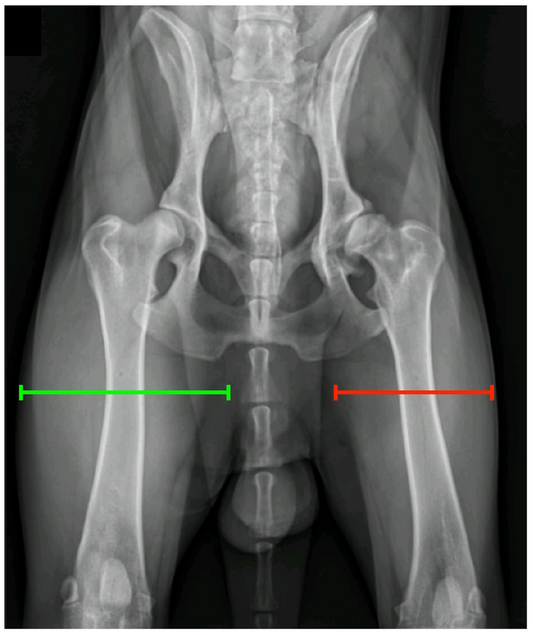

Figure 6: Ventro-dorsal pelvis x-ray of a dog with left sided hip dysplasia (the left joint is on the right of the image). Notice how the thigh muscle mass of the right side (green line) is much larger than that of the left side (red line). A guide to the success, or lack thereof, of medical management of CHD lies in the monitoring of thigh muscle bulk and whether it is increasing (success) or decreasing (failure) over time.